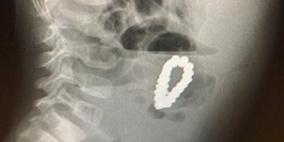

أطباء يعثرون على 18 قطعة مغناطيس في بطن طفل (شاهد)

استخراج 209 كرات مغناطيسية من معدة طفل